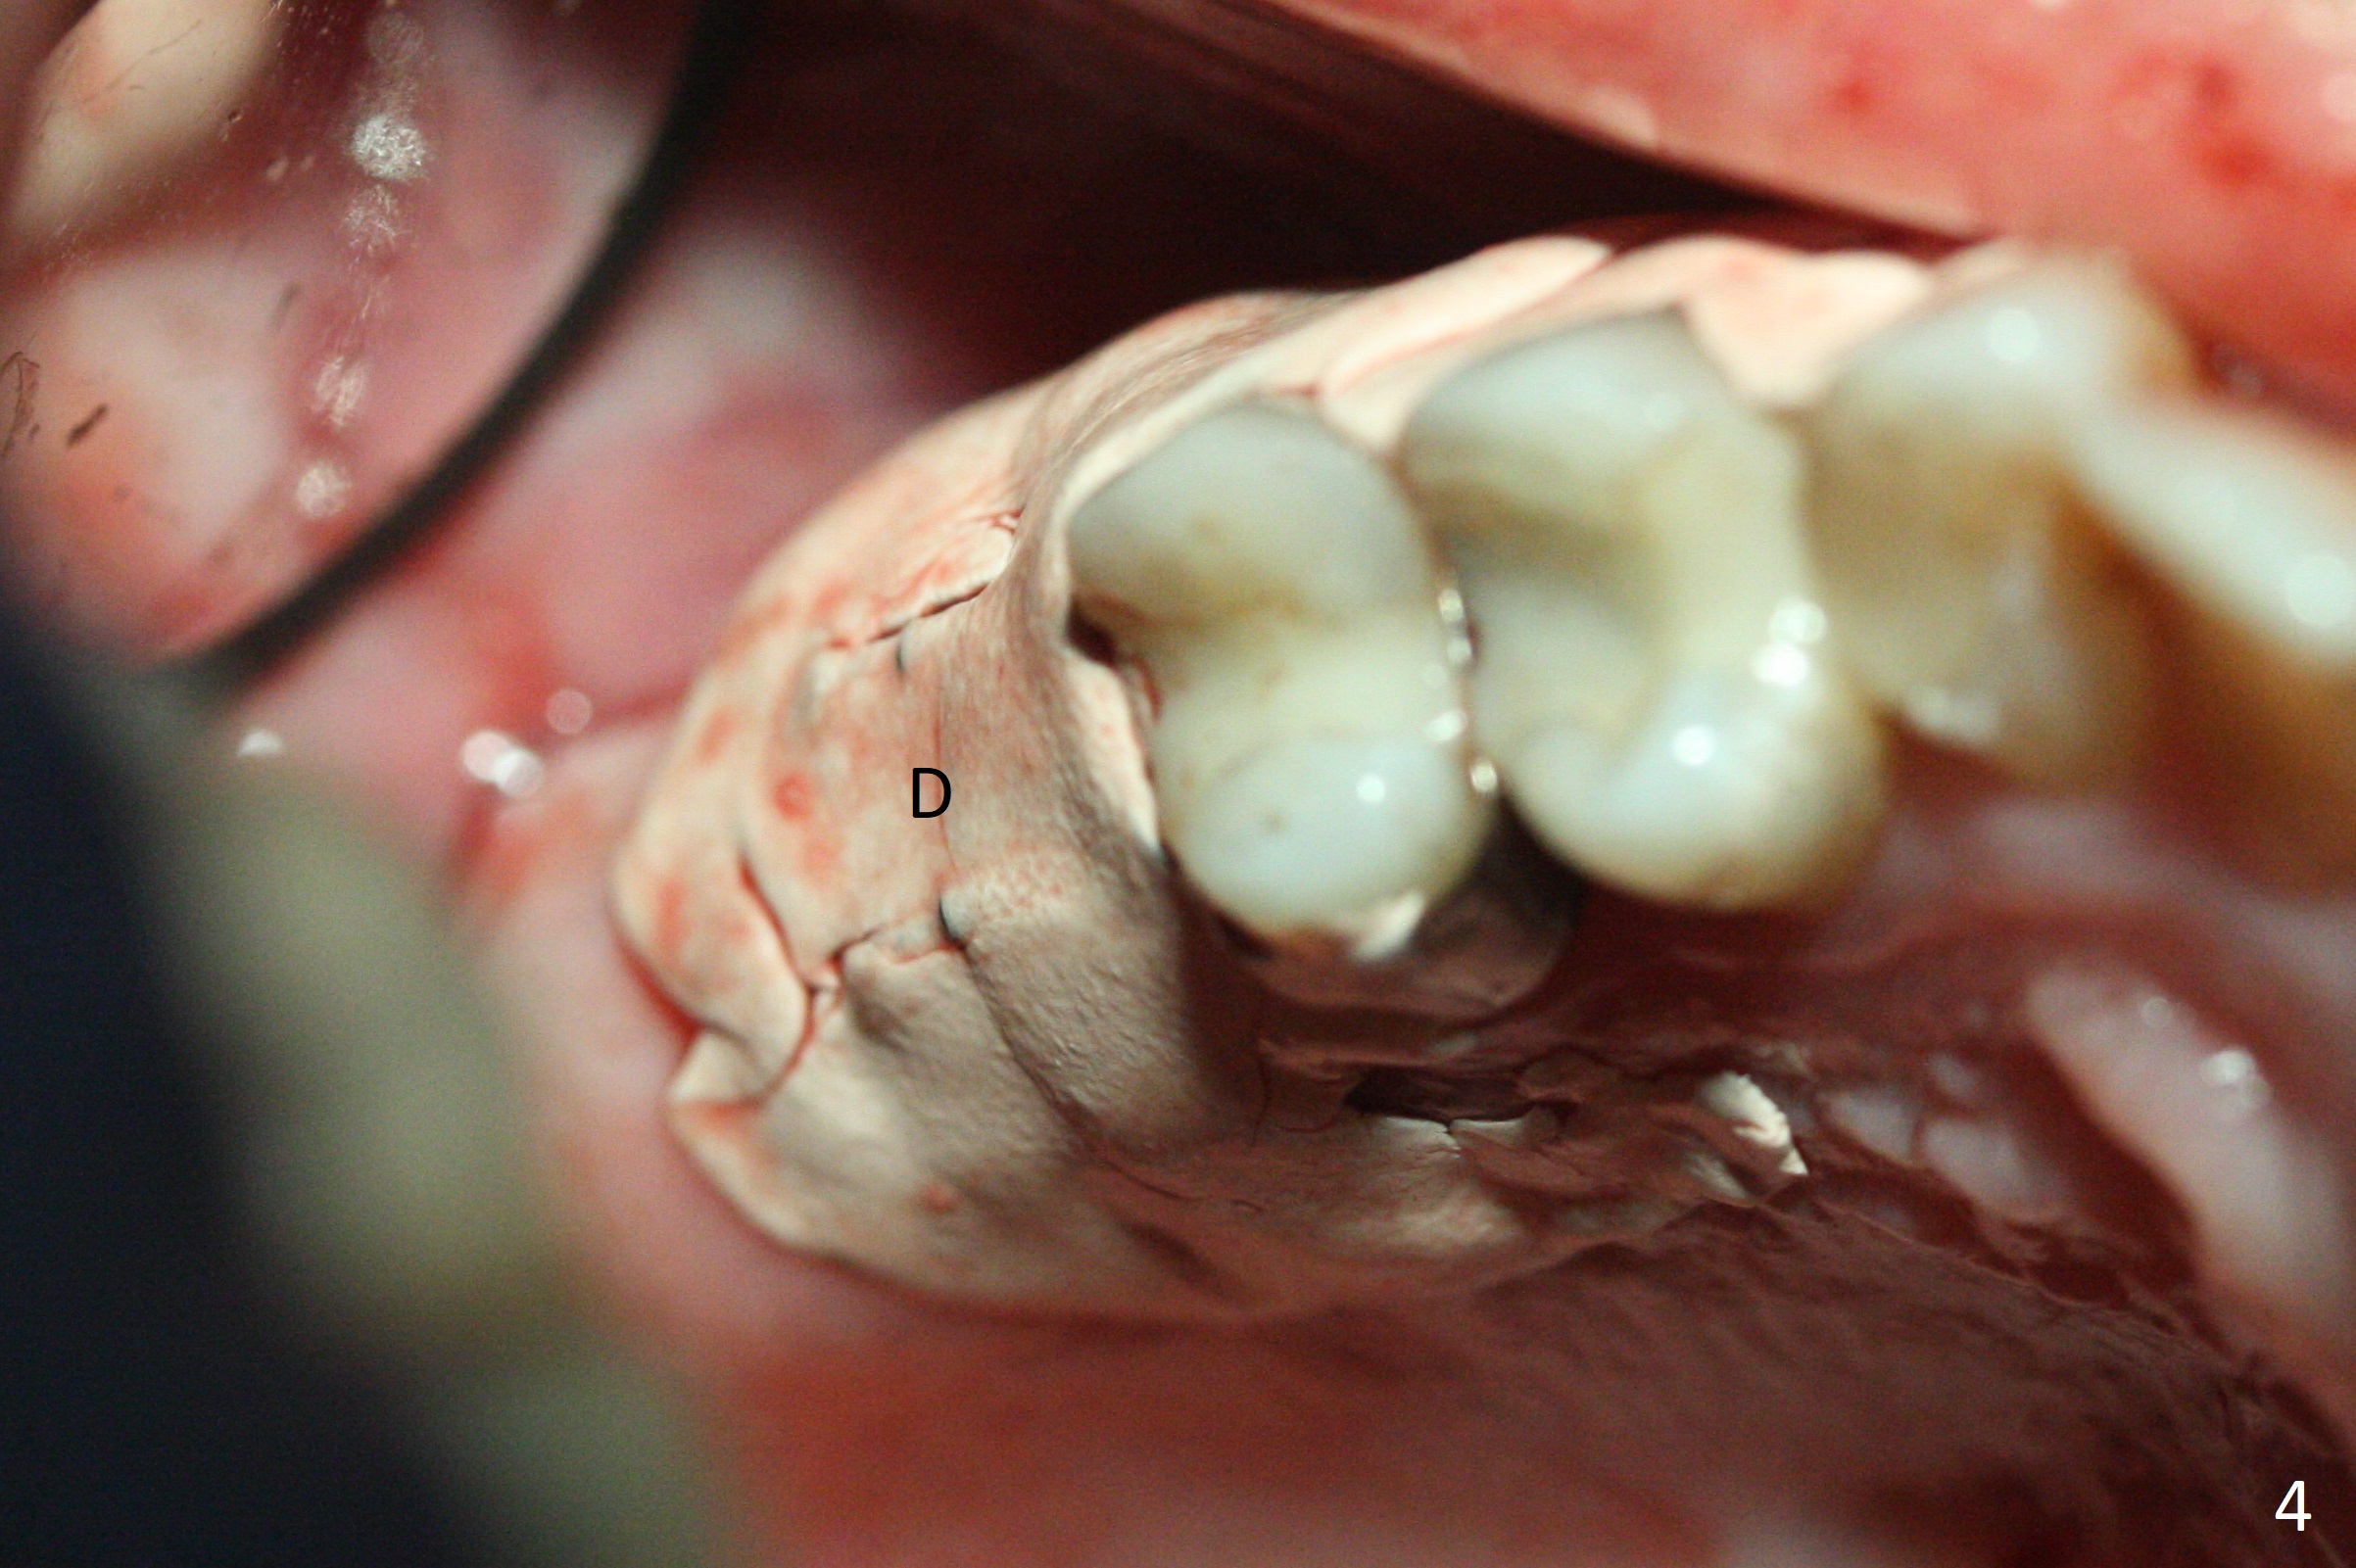

A 53-year-old woman wants to extract the tooth #3 with recurrent apical periodontitis (Fig.1). Socket preservation is conducted (Fig.2). The tooth is terminal in the arch and difficult to keep periodontal or acrylic dressing in place. To overcome the situation, a prefabricated space maintenance is placed without cementation because of its inherent fitness (Fig.3). Periodontal dressing (Fig.4 D) appears to be retained in place. The spacer is lost prematurely due to no cement, but the wound appears to be healing 13 days postop (Fig.5,6). The socket heals 3 months postop (Fig.7,8). However the ridge is narrow 19 months postop (Fig.9, as compared to that of the tooth #14 (Fig.10)).